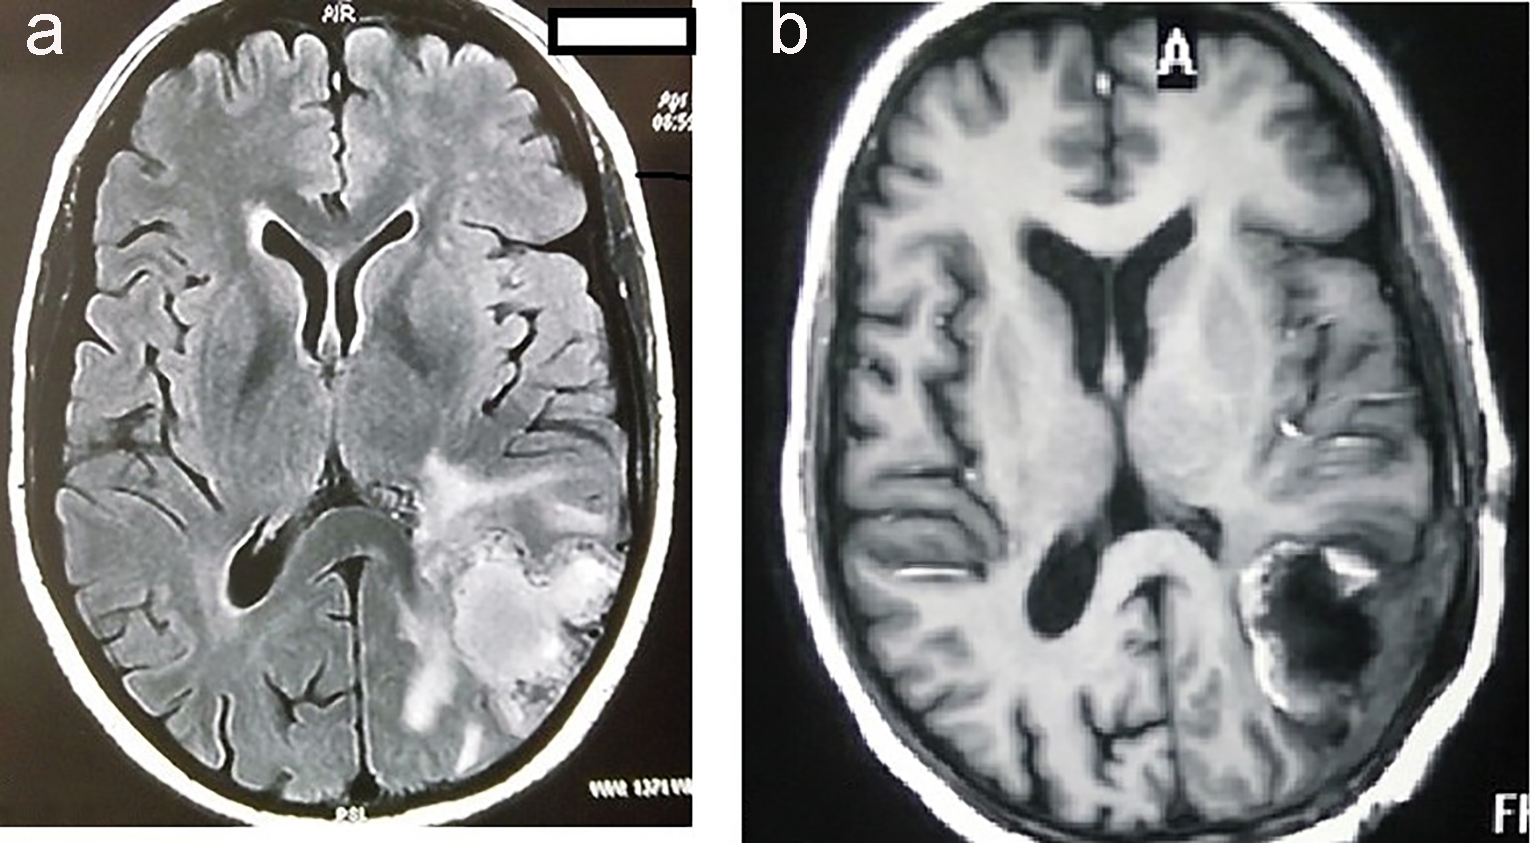

A 35-year-old female presented to neurosurgery department of our institute, with complaints of predominantly left-sided headache, vomiting and right-sided weakness for the last 2 months. There was no associated history of seizures, visual disturbances, fever or loss of consciousness. Magnetic resonance imaging (MRI) of brain showed heterogeneously enhancing mass measuring 4.9 × 8.4 × 4.5 cm with large central necrosis and perilesional edema seen in parieto-occipital lobe (Fig. 1a). A complete metastatic workup was done, which showed no evidence of disease elsewhere. Mass was completely excised in the neurosurgery department (Fig. 1b).

![]() Click for large image | Figure 1. MRI of brain showing hyperintensity in the parieto-occipital lobe of brain (a). MRI of brain showing postoperative defect after complete excision of tumor (b). |